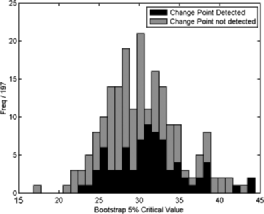

Figure 8 shows four typical examples of bootstrap distributions with and without changes detected. While differences due to the different underlying correlation structures are clearly visible, no difference is apparent between scans which contain a detected change and those which do not. Figure 9 shows the distribution of the 5% bootstrap critical values from 197 scans, once more indicating that the critical values show some deviation between scans due to different underlying correlation structures, hence different limit distributions, but do not differ between those with or without changes detected.

After the preprocessing of the data described in Section 2, a separable functional principal component decomposition was found, based on the three orthogonal directions within the image acquisition. Eigen-decompositions of the empirical covariance functions were used to generate the full three-dimensional functional basis. The eigenvalues associated with the decompositions did not decrease particularly fast. Indeed, the first 1000 eigenvalues only explained approximately 5% of the variation. In many applications, this is unappealing as it means that the data cannot be sparsely represented. However, in change-point detection, a flat eigenstructure in the uncontaminated covariance can actually (and somewhat counter-intuitively) enhance detectability and is therefore actually an advantageous property. By Corollary 5.1, change-points, if present, will tend to be found in eigenfunctions with larger relative eigenvalues, and hence only a small number of components need to be checked, especially when the components are flat. Thus, the number of components to examine was set to a small number, namely, systems with 64 () and 125 () eigenfunctions were investigated, with each direction having either its top 4 or 5 eigenfunctions as part of the tensor product. This was a compromise between having a large number of components, which would reduce the finite sample detectability as well as computational speed (processing time in Matlab for one scan with 1000 bootstrap samples for 125 components was approximately 6–7 hours on a desktop PC, while processing for the entire 197 scans took approximately 24 hours on a 40 node cluster), and having a sufficient number of components not to miss possible changes. Since the original data set was of dimension , systems with 64 and 125 eigenfunctions correspond to an approximate dimension reduction by a factor of 2000 or 1000, respectively. Three examples of the projected data of dimension 64 were discussed in Section 4.